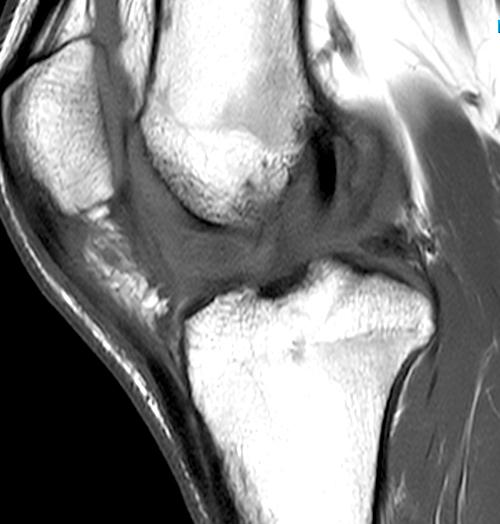

From radsource.us

Arthrofibrosis of the Knee Radsource Scar Tissue In Knee Patella Patellar clunk syndrome is a painful, palpable clunk that can occur at the patellofemoral articulation of a posterior stabilized tka caused. Scar tissue from arthrofibrosis can severely impact your knee’s range of motion. Flexion (bending) is affected by virtue of the patella being 'stuck down' with the adhesions and scar tissue. Later on the scar tissue under the patellar. Learn. Scar Tissue In Knee Patella.